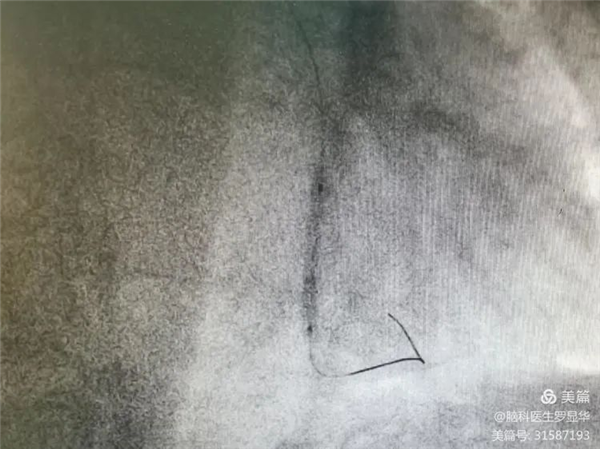

釋放冠脈球擴支架